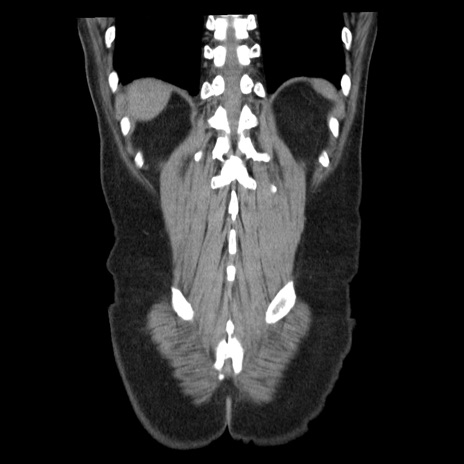

症例29(冠状断像)

【症例】40歳代男性

【現病歴】2日前から胃痛あり。徐々に周期的な激痛に変化した。本日になっても激痛があるため受診。

【身体所見】意識清明、BT 38-39℃台あり、腹部:膨満、やや硬、右下腹部に圧痛あり。

【データ】WBC 8500、CRP 23.26